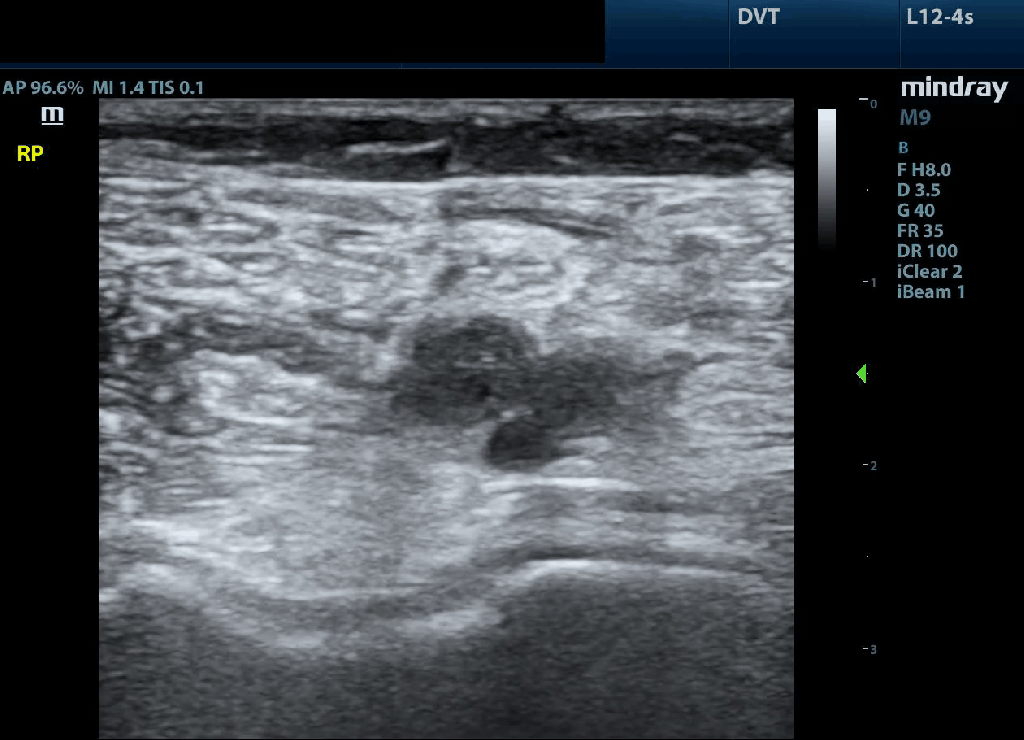

Positive: In this clip even before compression a hypoechoic structure within the lumen of the common femoral vein at the level of the lateral perforator can be seen but is PROVEN with in ability to compress. This is diagnostic for thrombus.